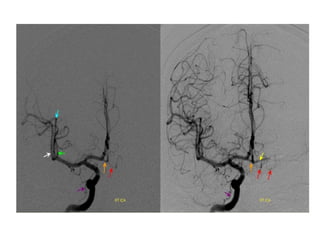

Anomalies of MCA

• Rare compared to other intracranial

arteries

Main anomalies include

• duplication

• accessory

• fenestration

Anomalies of MCA •Rare compared to other intracranial arteries Main anomalies include • duplication • accessory • fenestration